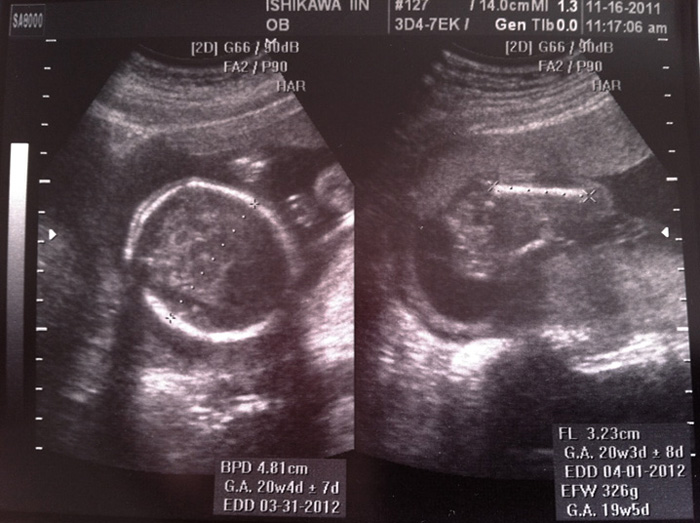

日本で初めての検診。隣町の医院で久しぶりの内診と超音波の結果、胎盤もしっかり出来上がり、骨も内蔵も確認する事ができ元気に育っていた。日本では初診になるので、改めて血液検査。それにしても日本の検診は手厚い。毎回行う超音波検査をDVDに焼いて頂き、毎回ここに記録してくれるらしい。

現在20週、重さは約300g。左が頭、右が大腿部。これからどんどん大きくなるんだよー。